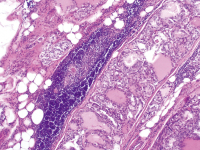

Der Schilddrüsenfall: Vermeintliche Sarkoidose erweist sich als pulmonal metastasiertes papilläres Schilddrüsenkarzinom

Journal für Klinische Endokrinologie und Stoffwechsel - Austrian Journal of Clinical Endocrinology and Metabolism 2016; 9 (2): 46-47 Volltext (PDF) Abbildungen